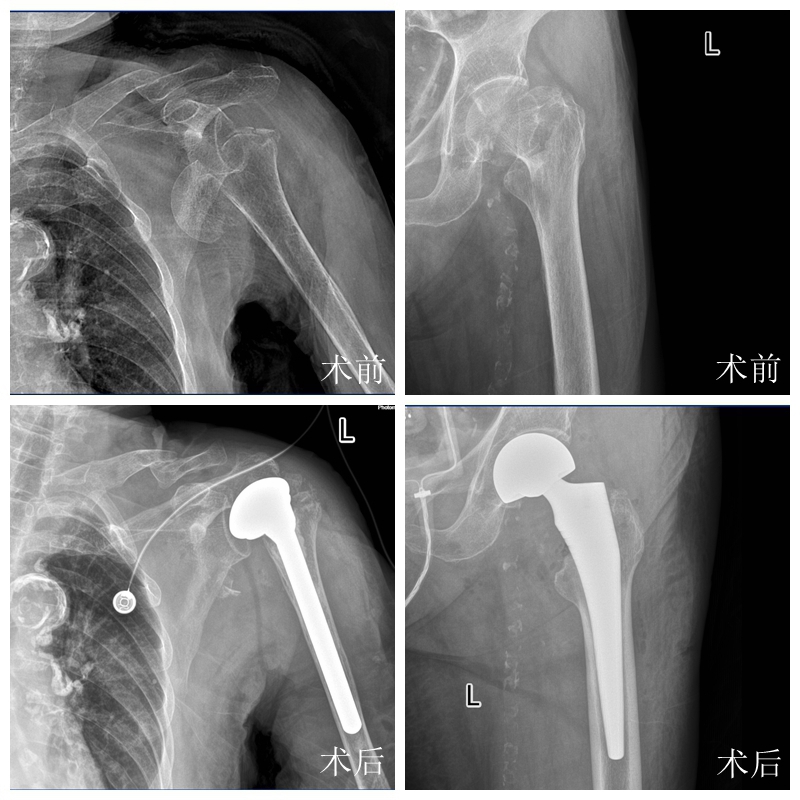

突破高龄手术禁区!95岁阿婆一次置换两关节

意外发生在不久前,蔡阿婆不慎摔伤,肩部和髋部剧烈疼痛,当场就动都动不了,被家人紧急送到我院就诊。

检查结果让所有人都揪紧了心:肩关节、髋关节同时骨折,亟须手术治疗。更严峻的挑战在于,老人长期心脏功能不全,患有慢性肺部疾病、贫血、低蛋白血症等多种基础疾病,入院时已经出现严重的电解质紊乱,身体虚弱得连呼吸都有些费力。

手术当天,由创伤关节外科主任陈文辉领衔的手术团队,凭借多年积累的复杂关节置换经验和娴熟的微创技术,医护人员默契配合、沉着应对。

从肩关节置换到髋关节置换,两台高难度手术衔接流畅,全程比预期更为平稳,成功为老人重塑了运动功能。